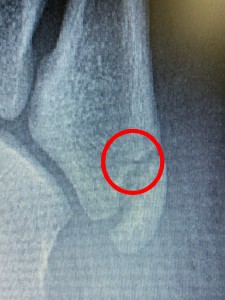

けど、第五中足骨の骨頭を触れると明らかに他の部位とは違う反応が❗️

結果、折れてました😅

この骨折、いわゆる下駄骨折って言って下駄履いて転んだらよくなるやつなんです❗️